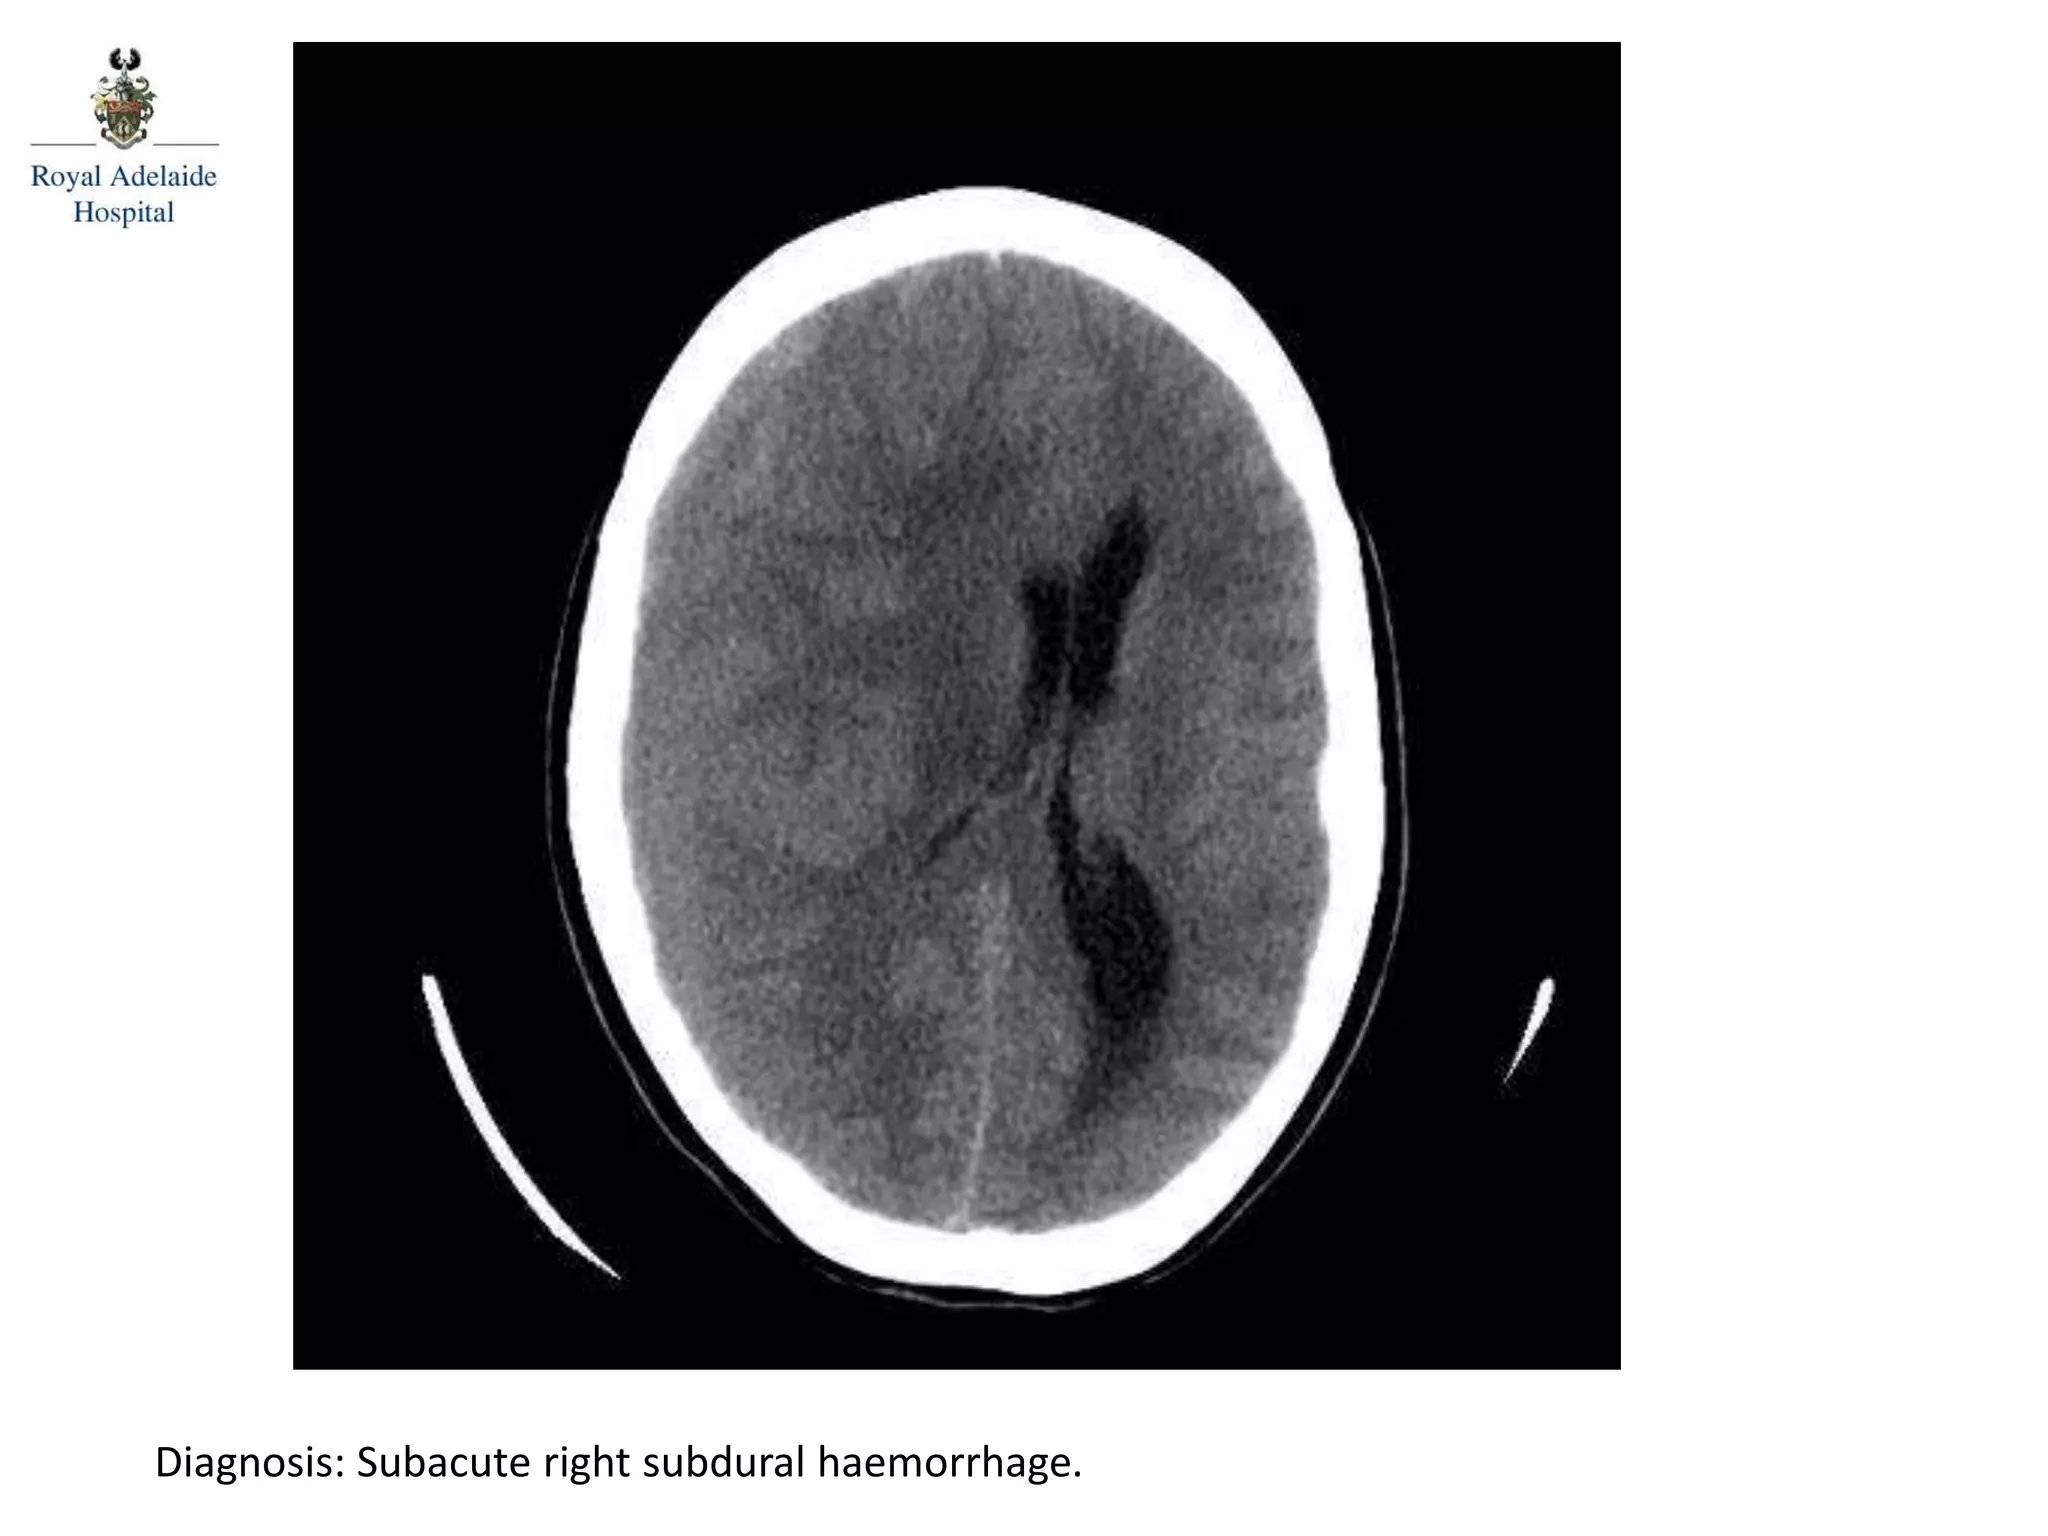

The document outlines multiple diagnoses from head CT cases, including small left basal ganglia bleed likely due to hypertension, various types of subdural and subarachnoid hemorrhages, and evidence of hydrocephalus. It details traumatic origins of some hemorrhages and notes obstructing masses and atrophic changes. Overall, there are significant findings indicating complications related to cerebral hemorrhages and ventricular enlargement.